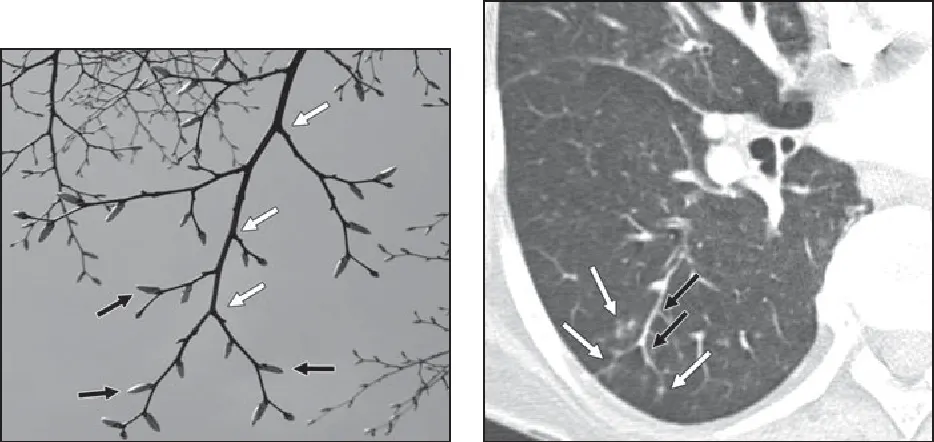

•

경계가 분명한 2~4 mm 크기의 nodules 또는 branching

Tree-in-bud sign : 의미. 흔함.